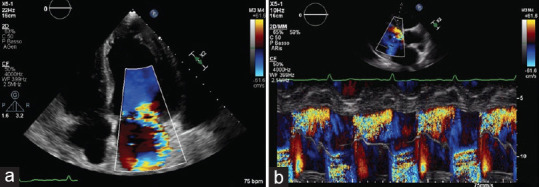

Left ventricular noncompaction (LVNC) is commonly described as a congenital cardiomyopathy characterized by prominent myocardial trabeculae and deep intertrabecular recesses extending in the left ventricular chamber. Clinical presentation can differ considerably from asymptomatic individuals to those presenting with heart failure and other serious complications. Diagnosis is usually made by two-dimensional transthoracic echocardiography or cardiac magnetic resonance. Moreover, even if strain parameters are significantly reduced in patients with LVNC, they are not routinely investigated. Here, we report the case of a previously symptomless patient admitted to the hospital for pulmonary edema. Two-dimensional transthoracic echocardiography showed severe valvular heart disease and left ventricle pronounced trabeculation and remodeling, although speckle tracking echocardiography (STE) demonstrated only mild strain reduction. We, therefore, explore the possibility that STE may be useful to differentiate LVNC cardiomyopathy from LVNC phenotype due to severe remodeling.